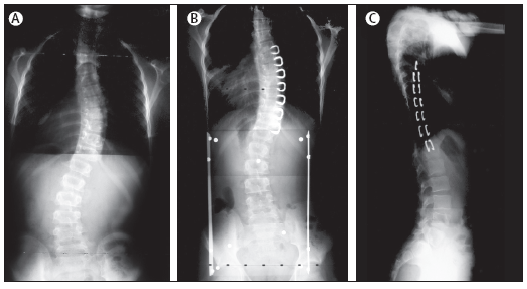

Figura

1. Screening e diagnosi di scoliosi mediante scoliometro

(Nota 1) e radiografia

A.

Misurazione della rotazione del tronco con uno scoliometro con

paziente in posizione di flessione anteriore

B.

Posteriore anteriore in un ragazzo di 13 anni, con un angolo di Cobb

di 30 gradi

Nota

1. Scoliometro (Dott. Paolo Becherucci). La dotazione

dell'ambulatorio del Pediatra di Famiglia. GIORNATE PEDIATRICHE

D'INVERNO. Madonna di Campiglio 2002

Lo

scoliometro è un semplice strumento la cui parte principale è

una pallina di mercurio che scorre in un canale curvo e si sposta in

base al dislivello fra i due lati dello strumento. L'incisione che

si vede nella figura si pone sopra l'apofisi spinosa delle

vertebre; è un utile complemento alla prova della flessione

anteriore per la scoliosi e permette di quantificare l'entità

del gibbo e quindi di confrontarne l'evoluzione nel tempo. Non

necessita di particolari attenzioni per la manutenzione; si trovano

modelli anche di basso costo ugualmente validi